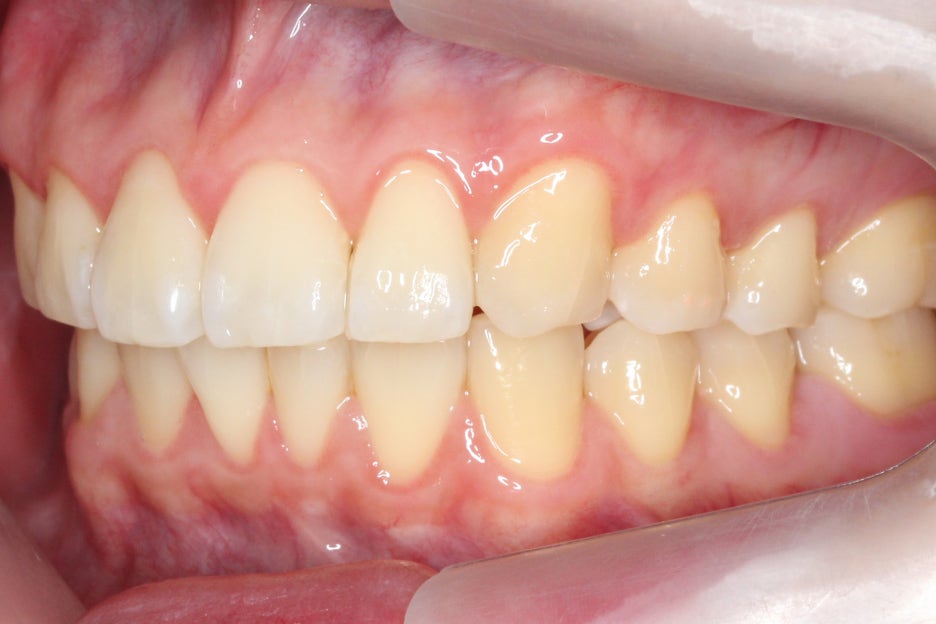

교정 후 협측 모습을 보면 전치부 치열이

돌출된 곳 없이 고르게 바뀐 모습을

확인할 수 있는데요,

문제가 있던 중절치가 개선되어

전치부의 스마일라인도 정돈된 모습입니다.